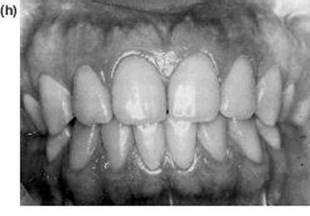

Clinically there is an increased overjet which is usually exaggerated by the lower lip being trapped behind the upper incisors, increasing their proclination and spacing (Figure 10.7). Externally this is seen as an everted lower lip exaggerating the labiomental groove.

Figure 10.7 Surgical correction of mandibular retrognathism by a sagittal split advancement, after orthodontic incisor retroclination and levelling of the occlusal plane. Note to dramatic improvement of the lower lip contour as well as the skeletal profile. (a) to (c) Preoperative and preorthodontic therapy. (d) to (f) Postorthodontic therapy and surgery.